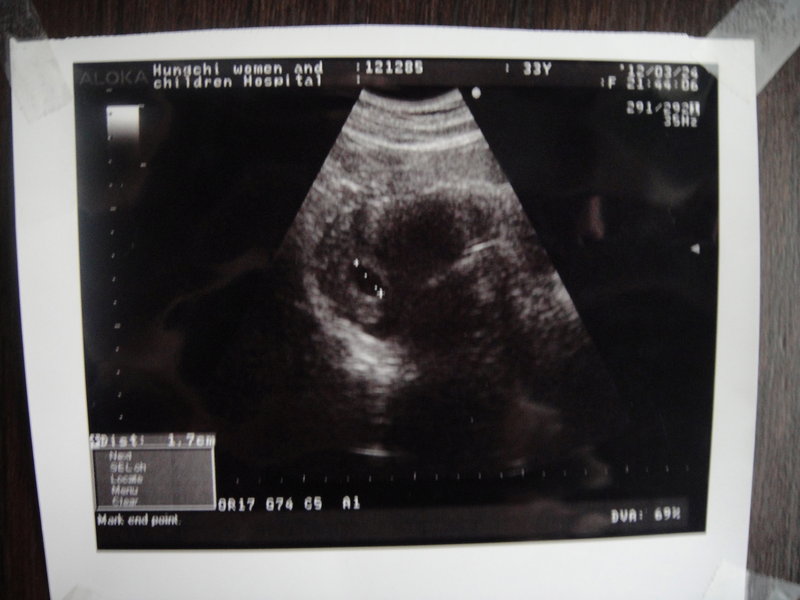

醫生說子宮後傾,初期容易照不到!還好....龍寶順利出現了!!

醫生幫我照超音波時說我子宮後傾,初期不容易照到!!

醫生說 龍寶的位置是正常的 胎囊的大小是1.7mm也很正常 ,過兩週再去聽心跳..